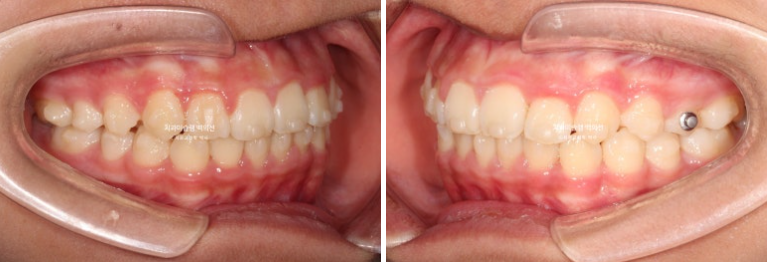

24년 1월 교정치료를 위해 온 만 10세 어린이 입니다.

3년 전에 소아치과에서 앞니 부분교정을 한 적이 있다고 합니다.

그래서 위 앞니에는 중절치 두 개를 잇는 철사유지장치가 붙어있었습니다.

중심선이 약 2mm 어긋나 있으며 위 앞니 치축은 한쪽으로 기울어져 있습니다.

앞니가 깊게 물리는 과개교합도 보입니다.